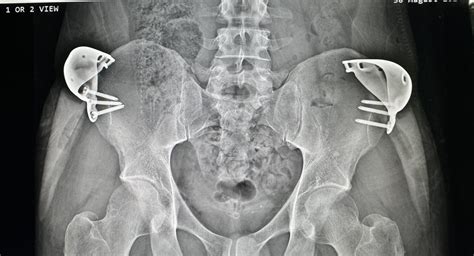

Hip Implant X Ray

Hip implants have revolutionized the field of orthopedics, providing relief and improved mobility for countless individuals suffering from hip joint issues. One of the critical aspects of managing hip implants is the use of hip implant X-ray imaging. This diagnostic tool plays a pivotal role in the pre-operative planning, post-operative monitoring, and long-term management of hip implants. Understanding the importance and process of hip implant X-ray imaging can help patients and healthcare providers make informed decisions.

The Role of Hip Implant X-Ray

Hip implant X-ray imaging is an essential diagnostic tool used to evaluate the condition of the hip joint and the implant itself. It provides detailed images that help orthopedic surgeons assess the alignment, positioning, and integrity of the implant. This information is crucial for both pre-operative planning and post-operative monitoring.